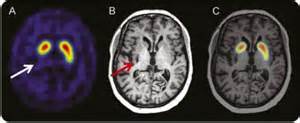

图:眩晕症的检查图

图:眩晕症的CT检查图

图:眩晕症CT检查